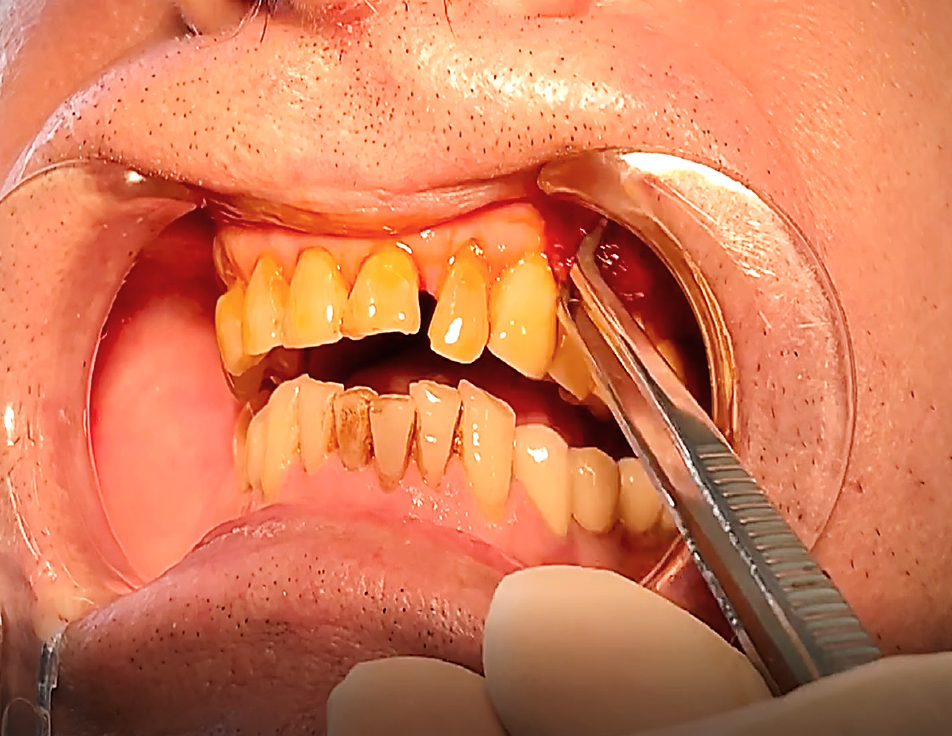

Метод гингивэктомии применяется достаточно часто при разрастании десневой ткани в ротовой полости. Данная стоматологическая манипуляция подразумевает отсечение лишней части мягкой ткани при помощи скальпеля. Данный метод применяется крайне редко, в основном у пациентов с «десневой» улыбкой [5]. После проведения процедуры обязательно проведение антисептической обработки и наложение специальной повязки на 48 ч, для предотвращения инфицирования и быстрого купирования воспалительного потенциала [6].

Клинический успех лечения оценивали путем соотношения шансов, который выражается соотношением повышенного риска и нормальной восприимчивости. Для определения факторов риска, так называемых факторов-предикторов, которые могут спровоцировать развитие воспаление зубодесневого комплекса, применяли следующие индексы – приблизительный индекс зубного налета – API, индекс сосочковой кровоточивости (PBI), пародонтальный индекс нуждаемости в лечении (CPITN), индекс рецессии десны по Miller. Алгоритм диагностики и ведения пациентов заключался в следующем. Проводилось комплексное поэтапное обследование. На первом этапе собран анамнез жизни и заболеваний пациента с выявлением существующих рисков (приобретенный или генетический уровень). На втором этапе произведен сбор клинических данных до начала проведения подготовки к ортопедическому лечению: оценка пародонтального статуса, уровня рецессии десны, вовлечение фуркации, активность карманов, подвижность зубов, оценка воспаления десны с проведением гигиенических индексов (рис. 2).

На первостепенном уровне проведена запись клинических данных («золотой стандарт»). Затем выполнена визуальная диагностика с помощью стоматологического зеркала, особо внимание уделяли скоплению зубного налета, выявление рецессии десны (рис. 3). Клинический осмотр на каждом этапе включал измерение глубины зондирования кармана и потери прикрепления (рис. 4). Сила зондирования составляла 0,20 Н, что соответствует 25 г.

До начала проведения подготовки зубодесневого комплекса у пациентов с низкой коронкой опорных зубов была определена гигиена полости рта, на основании показателей которых выполнена профессиональная чистка зубов. Так, API составил 69 %, индекс сосочковой кровоточивости PBI – 28 %, CPITN – (2,1 ± 0,3) балла. При зондировании зубодесневой борозды глубина погружения определена в (2,7 ± 0,2) мм. Далее пациентам согласно рандомизации выполнена одна из методик подготовки зубодесневого комплекса к ортопедическому лечению – гингивэктомия, гингиворетракция и гингивопластика (рис. 5). Спустя 14 дней при оценке клинических показателей были получены следующие значения (табл. 1).